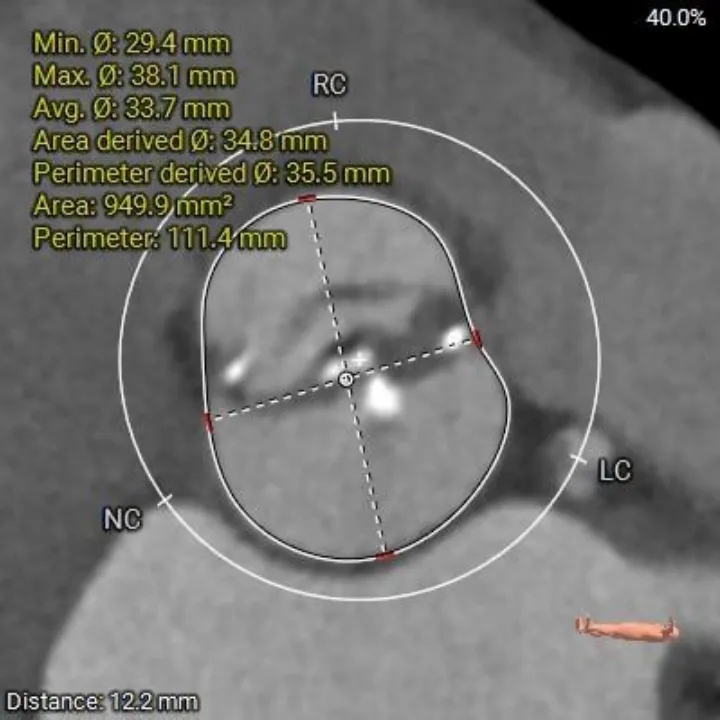

主动脉根部测量

Annulus

23.8mm

LVOT

22.4mm

横列式Type0型二叶瓣,瓣环内径23.8mm

流出道收口型

瓣上2mm

21.6mm

瓣上4mm

21.9 mm

瓣上6mm

21.7 mm

瓣上8mm

21.7mm

瓣上10mm

21.1mm

瓣下2mm

22.2mm

瓣上限制较重,可见明显左窦瓣叶偏心钙化,限制最重区域为瓣上4-8mm。